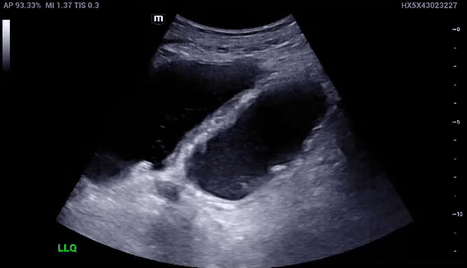

LBO: Ultrasound Findings

Diameter/Thickness

LBO on ultrasound will show a diameter of > 4.5 cm and thickness > 3 mm. The bowel wall is typically ≤ 3mm and ≤ 2 mm when distended

Haustra

Haustra are spaced and far apart. This differs from the plicae circulares of the small bowel.

A Lines

A-lines are reverberation artifacts seen on Ultrasound when beams interact with air. If seen inside the bowel, indicative of air-fluid levels inside bowels.

Abnormal peristalsis

“To and fro” movement of peristalsis indicative of obstruction. Normal peristalsis will have unidirectional flow

!!!Ultrasound has also been specifically evaluated for the diagnosis of LBO with a sensitivity of approximately 85% in one study!!